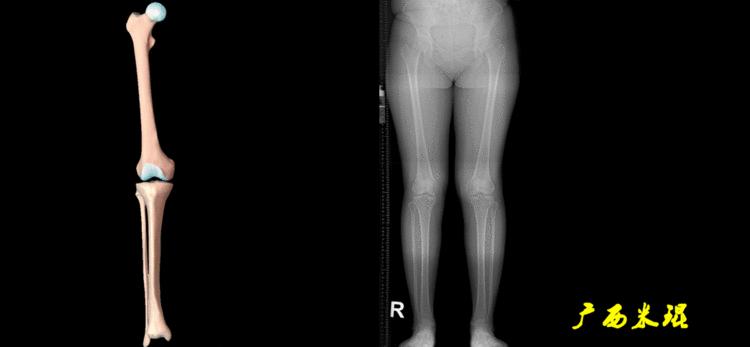

(1)解剖轴

股骨和胫骨的骨干中线为解剖轴,股骨解剖轴和胫骨解剖轴的夹角正常值为174°±1°。

提醒大家,解剖轴在平直的骨干中沿着骨干中间直线走行,在带弧度的骨骼沿着弧形的骨干呈弧形线走行。这样可以排除来自骨干部位的成角畸形,对骨干部位的成角畸形矫正处理上与近关节处畸形的共同点为截骨要靠近畸形处。

(2)机械轴

机械轴是连接近端和远端关节中心点的直线。

机械轴要分前后位及侧位,站立前后位(也就是冠状面)股骨头中心与踝关节中心的连线通过膝关节中心,这是下肢的机械轴线,也就是下肢力线,常说Mikulicz线。冠状面的力线评估在临床工作中最常用、最基础、最重要。

站立侧位(矢状面)股骨头中心与踝关节中心的连线也通过膝关节中心,这也是下肢的机械轴线,这也是下肢力线。

矢状面的下肢力线常常被医生忽视,其实它的改变也是膝关节疼痛的常见原因。